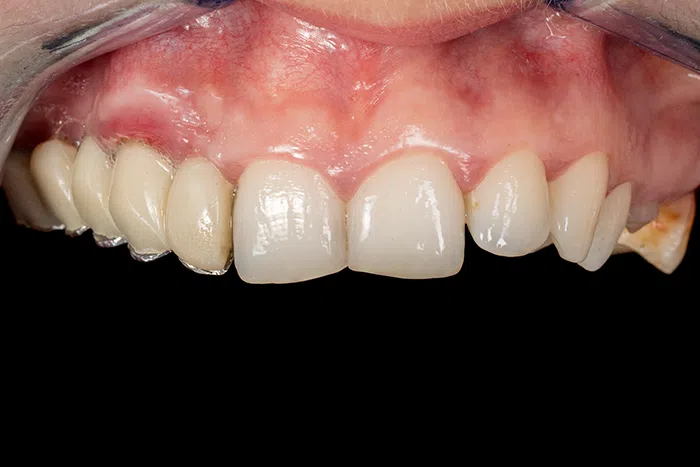

Caz de estetică dentară – Coroane ceramică presată E-Max

Provocarea acestui caz a fost tratarea minim invazivă a dinților restanți, în urma înlocuirii coroanelor vechi și obținerea unor dinți cu un volum mai mare pentru echilibrarea zâmbetului într-un aspect cat se poate de natural.

Pacientă a beneficiat de corecție gingivală cu laser pentru uniformizarea asimetriilor gingivale, tratamente endodontice de canal sub microscop, obturațiile vechi (plombe) schimbate cu materiale de compozit cu particule nanoceramice, și fațete dentare din ceramică presată E-Max.

Termen de finalizare 2 săptămâni de la amprentarea finală.